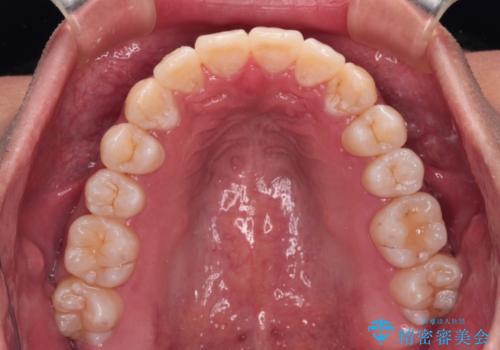

- 八重歯と飛び出している前歯を気にして来院された患者様です。

歯列としてはインビザラインでもワイヤー矯正でも対応できるものでしたが、上顎の八重歯や下顎小臼歯の捻転といったインビザラインでは時間のかかってしまう歯列不正が認められたため、補助装置やワイヤー矯正を治療当初に使用することで、インビザラインによる治療をスムーズに行えるように計画しました。